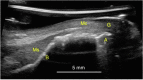

Background: Ultrasound is a non-invasive, cross-sectional imaging technique emerging in dentistry. It is an adjunct tool for diagnosing pathologies in the oral cavity that overcomes some limitations of current methodologies, including direct clinical examination, 2D radiographs, and cone beam computerized tomography. Increasing demand for soft tissue imaging has led to continuous improvements on transducer miniaturization and spatial resolution. The aims of this study are (1) to create a comprehensive overview of the current literature of ultrasonic imaging relating to dentistry, and (2) to provide a view onto investigations with immediate, intermediate, and long-term impact in periodontology and implantology.

Results: A critical review of the clinical applications of ultrasound in dentistry was provided with a focus on applications in periodontology and implantology. The role of ultrasound as a developing dental diagnostic tool was reviewed. Specific uses such as soft and hard tissue imaging, longitudinal monitoring, as well as anatomic and physiological evaluation were discussed.